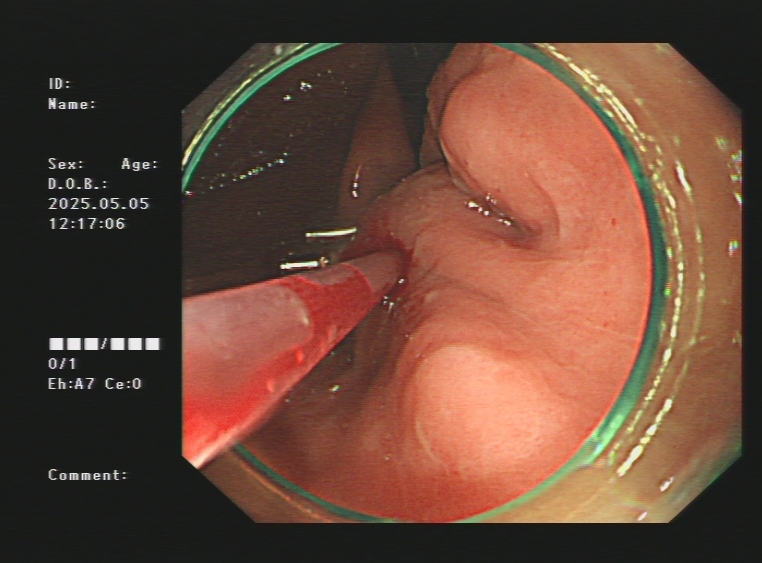

1.上消化道出血常见原因:消化性溃疡(胃溃疡、十二指肠溃疡)、食管炎、急性糜烂出血性胃炎、上消化道肿瘤(食管癌、胃癌)、剧烈呕吐造成的食管贲门黏膜撕裂伤、肝硬化引起的食管胃底静脉曲张。以下是一些常见的上消化道出血内镜图片:

急性胃黏膜病变出血、十二指肠球部溃疡出血及镜下止血夹止血